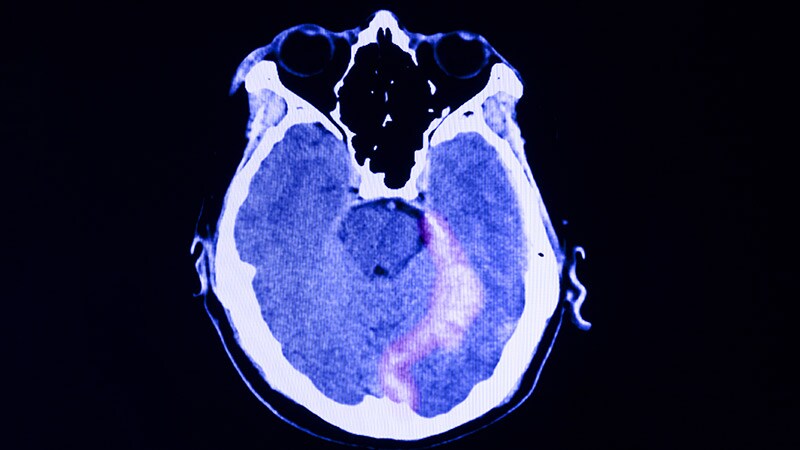

What Causes One of Stroke's Most Common Complications? -

Sharp Rise in Traumatic Brain Injury-Related Mortality -